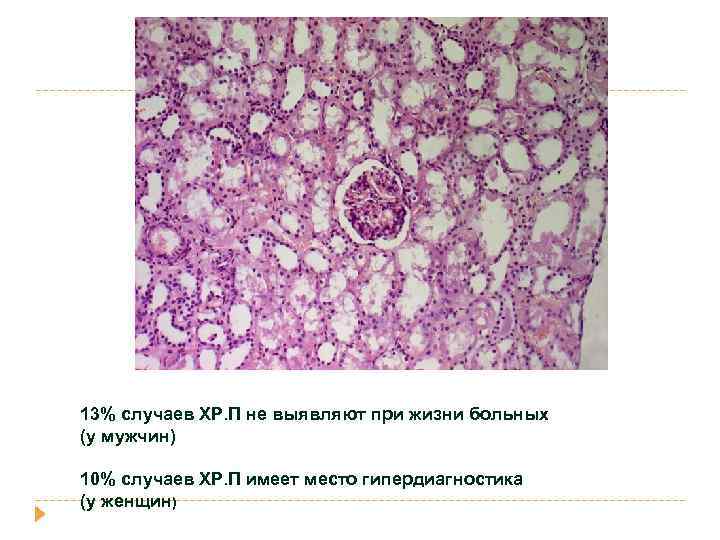

острый пиелоне фрит Гнойное воспаление с абцедированием Хронический пиелонефрит Лимфогистиоцитарная инфильтрация и склероз стромы, Перигломерулярный склероз Кистозная атрофия канальцев «тиреодизация почки» Ассиметричное сморщивание почек с грубыми рубцами

Хронический пиелонефрит

13% случаев ХР. П не выявляют при жизни больных (у мужчин) 10% случаев ХР. П имеет место гипердиагностика (у женщин)